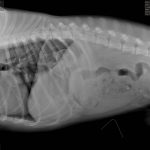

They Ate What?! X-ray Contest 2017They Ate This: Check out the winner, runners-up, and honorable mentions September 29, 2017 < Previous Entry Pages: 1 2 3 4 5 6 7 8 9 10 11 12 13 14 15 16 17